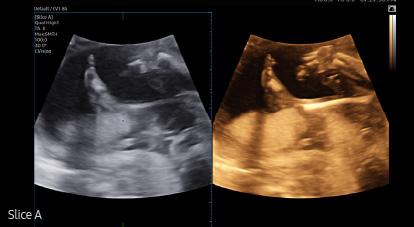

Slice A ¹, is a feature that improves the contrast resolution of A Plane images. By compositing multiple A Plane images, it helps in analyzing tissues or structures that are difficult to see with only 2D images.